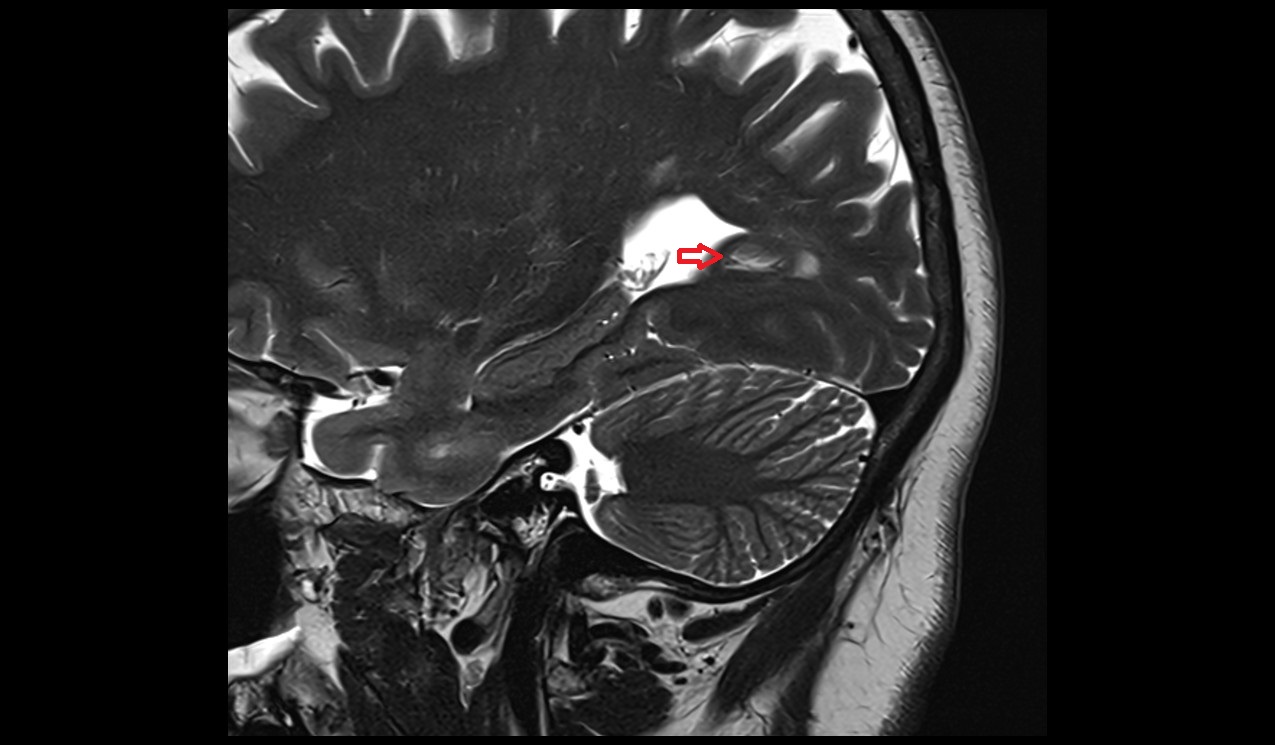

- Choroid fissure